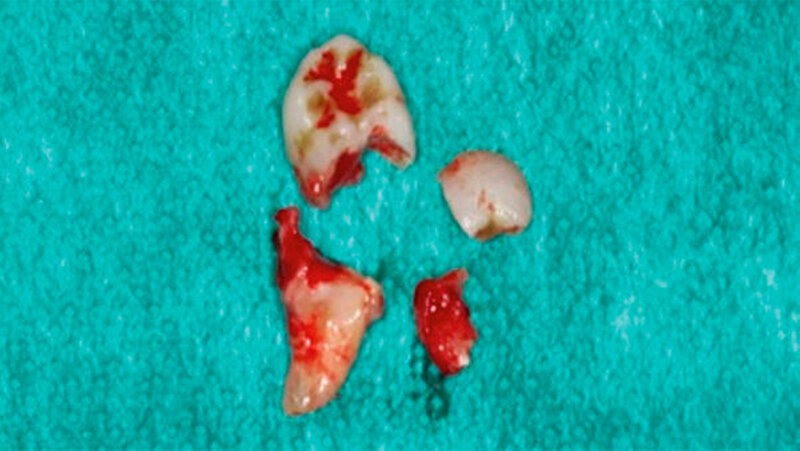

Der intraoperative Verlauf gestaltete sich komplikationslos. Sowohl der N. alveolaris inferior als auch der N. facialis konnten geschont werden. Der Zahn 38 wurde mitsamt dem umgebenden Granulationsgewebe vollständig entfernt. Die Abbildungen 3, 4 und 5 zeigen den operativen Vorgang und den entfernten Weisheitszahn. Die pathohistologische Aufarbeitung bestätigte die Verdachtsdiagnose einer entzündlichen Veränderung. Eine follikuläre Zyste konnte ausgeschlossen werden.